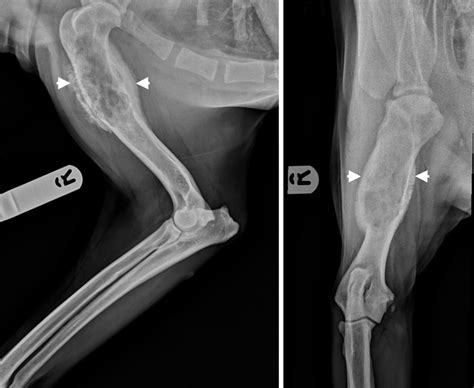

• Sunburst Pattern: Radiating spicules of bone formation that extend outward from the tumor into the soft tissue.

• Codman’s Triangle: A triangular formation of new bone that occurs when the tumor grows faster than the periosteum (the outer covering of the bone) can form new bone, resulting in an elevation of the periosteum.

• Soft Tissue Mass: Shadows outside the bone that suggest the tumor has breached the cortical bone and is invading the surrounding soft tissues.

Interpreting an Osteosarcoma X Ray requires a nuanced eye. Osteosarcoma is heterogeneous, meaning it can present in several different ways depending on its subtype and location. The appearance of the lesion often depends on whether it is predominantly osteoblastic (bone-forming) or osteolytic (bone-destroying).

• osteosarcoma x ray dog